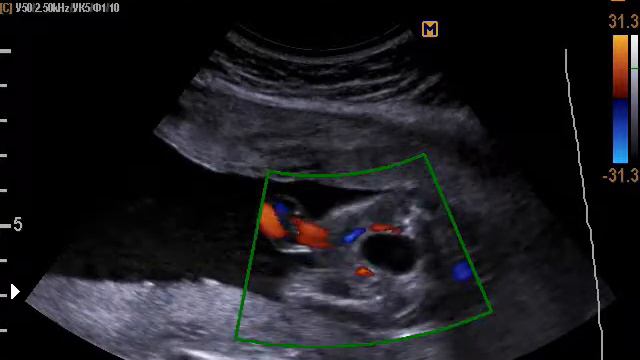

2 артерии пуповины

2 артерии пуповины 113 фото